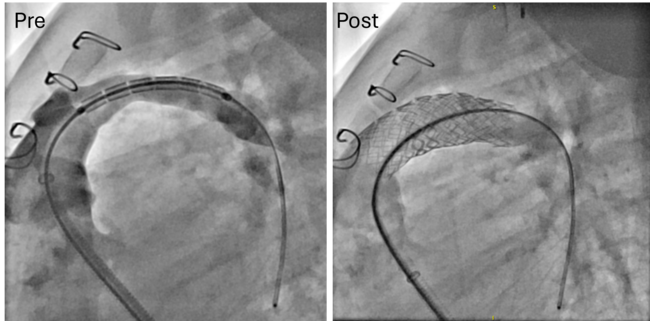

From a procedural standpoint, general anesthesia was utilized in 17 of the 23 procedures, while monitored anesthesia care was provided for the remaining 6 procedures. The patients typically underwent right heart hemodynamic catheterization, coupled with angiography for those with RVOTO, PAS, and SVS (Figures 1-3, pre). Additional retrograde left heart hemodynamic catheterization and angiography were performed for the patients with CoA (Figure 4, pre). The delivery sheath was as small as 7-French (Fr) in the femoral vein for the patients with RVOTO, PAS, and SVS, and 8-Fr in the femoral artery for patients with CoA, with ultrasound confirmation of a femoral arterial diameter greater than 3 mm prior to access in smaller patients. Stent size and pre-mount balloon diameter were chosen based on targeted pre-/post-stenotic vessel diameter, in addition to minimum waist diameter to allow secure delivery. Length was determined for adequate coverage of the targeted lesion. Rapid right ventricular pacing was performed only for CoA stent implantations. Selective post-implantation dilation with a non-compliant balloon was performed as needed to achieve the targeted diameter. Post-implant ultra-high-pressure dilation (≥ 20 atm) was performed on 8 stent grafts for full expansion (Table 2). Post-implantation angiography (Figure 1-4, post) and hemodynamic measurements were analyzed for all cases (Table 2).

The stent graft is also designed with independent tines rather than a continuous frame, conferring superior flexibility and enabling segmental flaring. This feature is advantageous for trackability over a wire in small pediatric patients, particularly those with branch PA stenosis (Figure 2). In addition, treatment of patients post-LeCompte maneuver may risk the creation of aorto-pulmonary fistula creation, so a covered platform is ideal.6 The flexible frame may allow for a more rounded implant shape contouring to the aorta. The non-contiguous frame also allows for segmental flaring; this creates a funnel into the stent that allows for ease of wire passage and entry upon re-intervention. The additional flexibility of this design leads to improved navigation through the calcified or acutely angulated regions of the RVOT, thereby delaying the necessity for surgical intervention in pediatric cases (Figure 1).